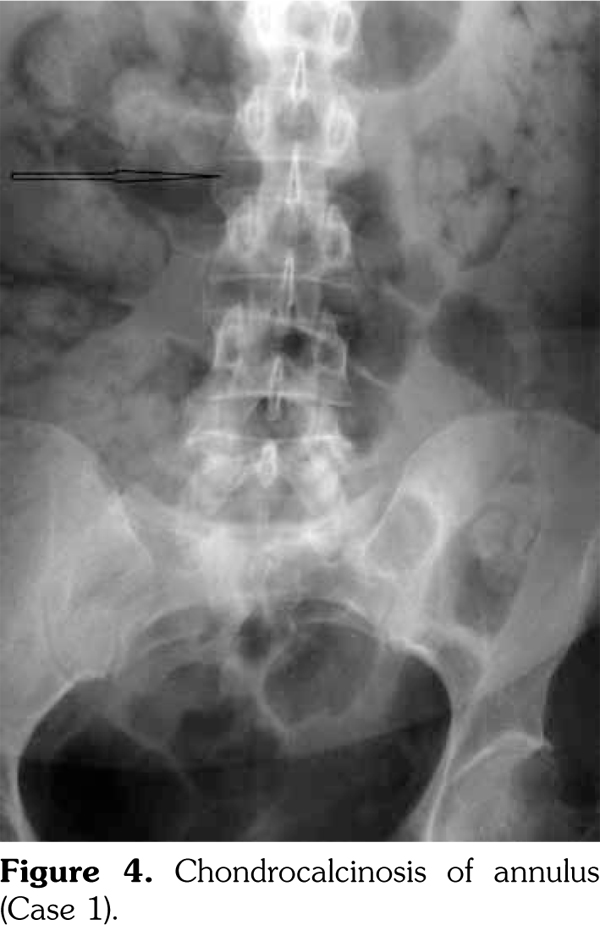

On examination, there was swelling and painful restriction of movement in her right knee. Imaging revealed calcification of cartilage of wrists, knee joints and hip joints although no microscopic confirmation was possible at this stage (Figure 1-4). She was investigated for a possible cause for CC, although investigations to screen for a metabolic cause turned out to be negative with a possibility for hereditary CC.